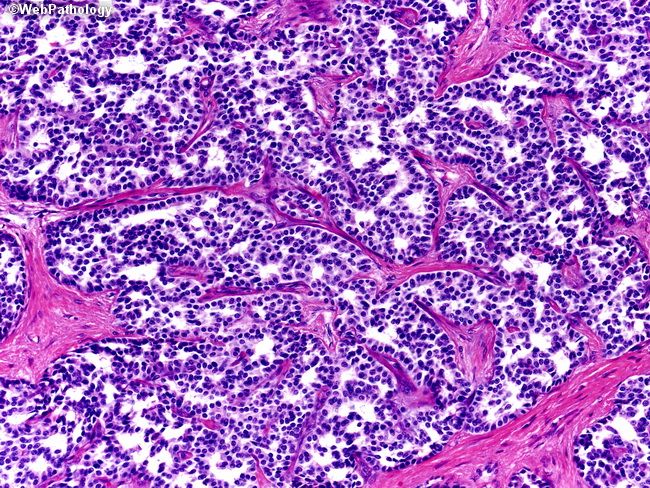

Гистологическое строение опухоли

Гистологическое строение опухоли 110 фотографий